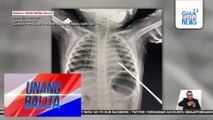

Ilang motorista at residente, na-stranded sa baha; baha, abot-dibdib | UB